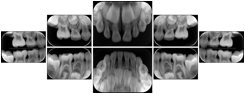

3. A dental provider wishes to capture a series of DICOM IO images for the patient’s dentition. The tooth morphology, teeth are divided into molars, premolars, canines and incisors, and a number of images for each jaw. The anatomic information was captured utilizing the triplet of schema. This standard code sequence is based on ISO 3950-2010, Dentistry - Designation system for teeth and areas of the oral cavity.

Every IO image should have anatomic information either through the primary or modifier sequence.

In most standard cases, images are oriented in structured layouts. These structured displays are useful to be shared between providers for reference purposes.

Table OO.1.1-1 shows structured display standard templates, where Viewset ID is based on the Japanese Society for Oral and Maxillofacial Radiology (JSOMR) classification provided by JIRA (Japan Medical Imaging and Radiological Systems Industries Association, www.jira-net.or.jp). Expected or typical teeth to be imaged location, region and designation codes are based on ISO 3950-2010, Dentistry - Designation system for teeth and areas of the oral cavity. For all the hanging protocols listed in OO.1.1-1, the value to use for Hanging Protocol Creator (0072,0008) is "JSOMR" and the value to use for Hanging Protocol Name (0072,0002) does not include "JSOMR" (e.g., "DL-S001A", not "JSOMR DL-S001A").